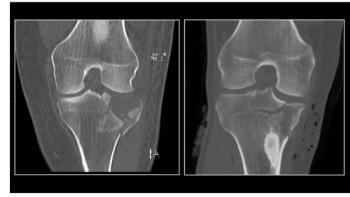

Ultra-low dose CT to detect joint fractures in children as good as standard CT imaging.